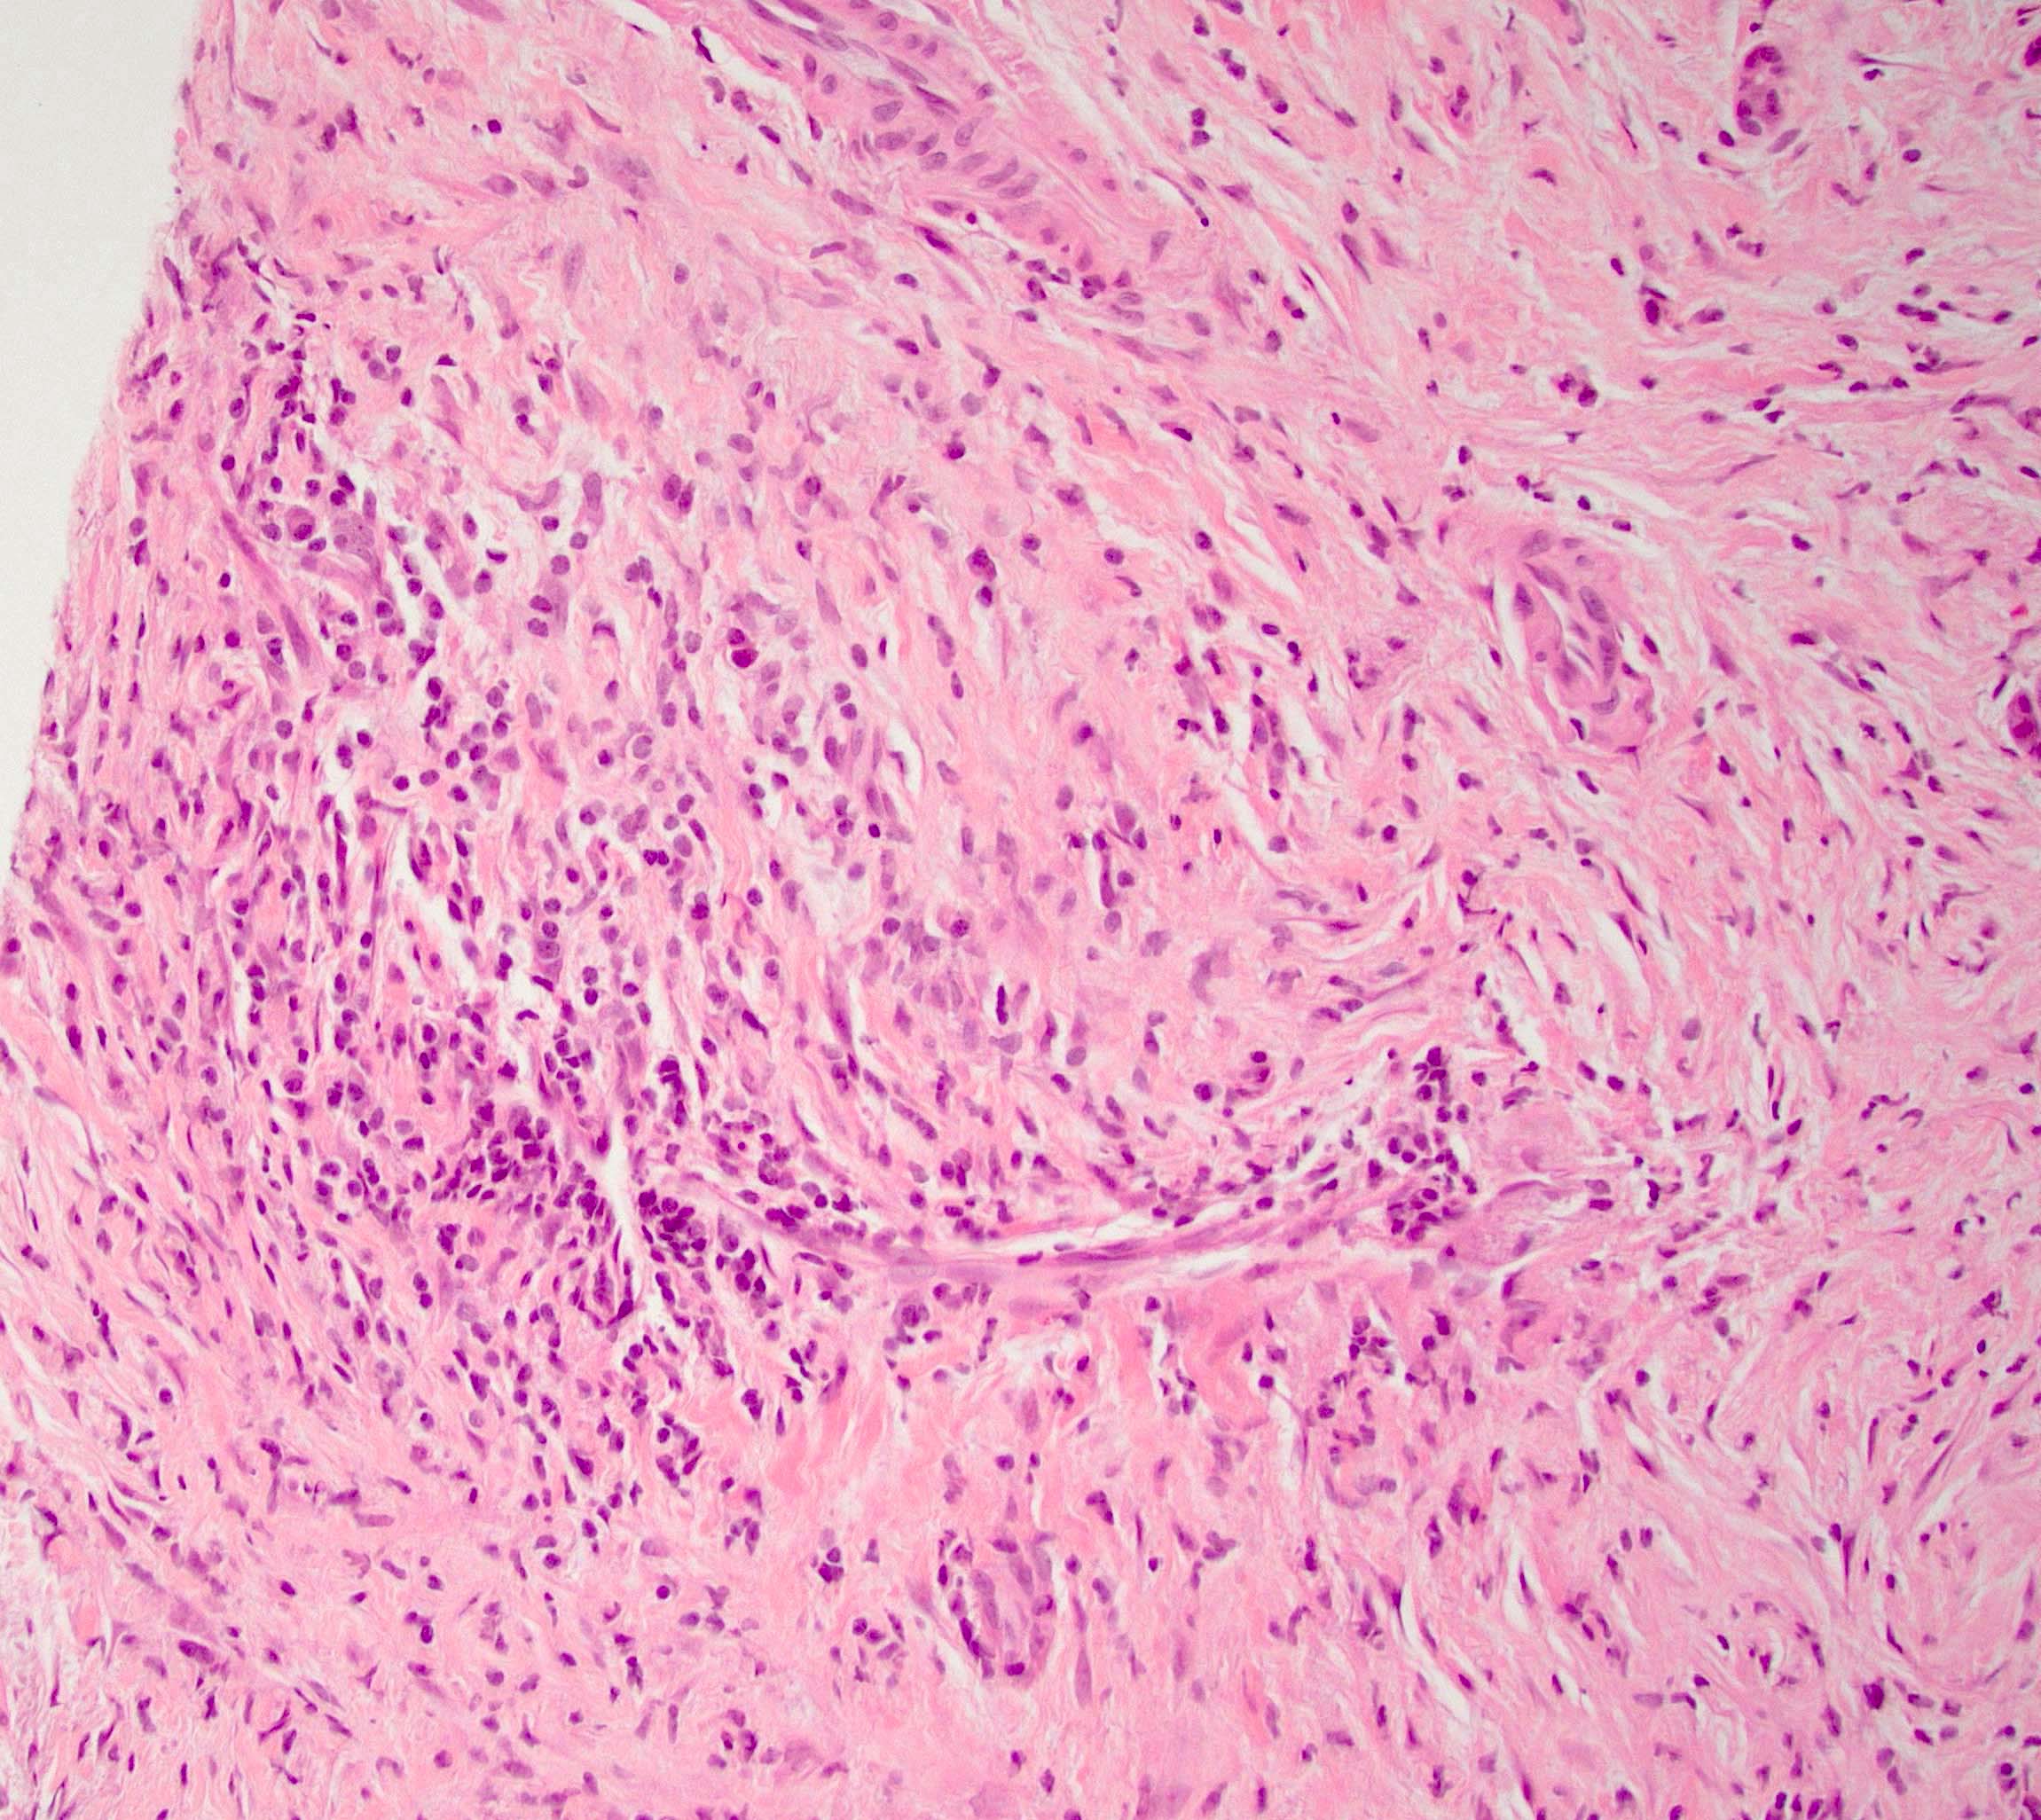

Microscopic (histologic) description

- Characteristic findings (at least 3 for level 1 criteria) (Pancreas 2011;40:352)

- Periductal lymphoplasmacytic infiltrate without granulocytic infiltration

- Obliterative phlebitis

- Storiform fibrosis

- Abundant (> 10 cells/high power field) IgG4 positive plasma cells

- Biopsy showing some but not all of the above features can be used as supportive evidence for the diagnosis of autoimmune pancreatitis (Pancreas 2011;40:352)

- Inflammation is localized within the pancreatic parenchyma and is centered around / within medium to large interlobular ducts, which causes shrinkage of the ductal lumen (Pathologica 2020;112:197)

- Inflammation can also be seen between the pancreatic parenchyma and peripancreatic adipose tissue (Pathologica 2020;112:197)

- Inflammation of the venous wall can progress to obliterative phlebitis with fibrosis of the lumen (Pathologica 2020;112:197)

- As the inflammation progresses, fibrosis becomes more diffuse, assuming a whorled or storiform pattern (Pathologica 2020;112:197)

- Perineural inflammation can also be present (Pathologica 2020;112:197)

Microscopic (histologic) images